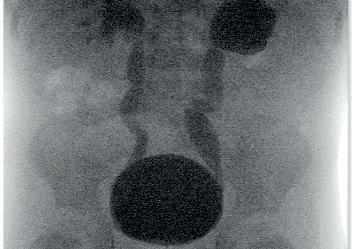

Abb. 1: Phimose. Abb. 2: Vesikoureteraler Reflux – prä- und postoperative Miktionszystourographie nach Ostiumunterspritzung.

Es ist nochmals zu betonen, dass jedes Kind, das mit dem Symptom des Bettnässens zum Arzt gebracht wird, hinsichtlich anderer Ursachen abgeklärt werden muss – in unserem Krankenhaus betreffen diese über 20 % der Patienten mit einer kindlichen Harninkontinenz. Sie reichen von neurologischen Ursachen wie Spina bifida über rezidivierende Harnwegsinfekte bis hin zu Urogenitaltraktfehlbildungen, z. B. dem vesikoureteralen Reflux, ektop mündenden Harnleitern, Harnröhrenklappen, Harnröhrenstrikturen, Meatusstenose, Phimose (siehe Abbildung 1) etc.